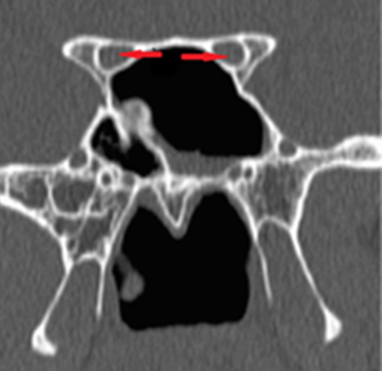

Optic nerve canals were categorized into four Types [Table/Fig-1] by our classification system based on improvisation of Delano et al., classification [3]. In Type-1 canal there is no protrusion of optic nerve into the canal [Table/Fig-2]. Degree of optic nerve protrusion into the canal was taken into consideration for better objective classification of Type-2 and Type-3 canals [Table/Fig-3,4]. Type-4 canal is posteriorly displaced in ethmoidal air cell (Onodi cell or spheno–ethmoidal air cell), projecting superolateral to sphenoid sinus and forming medial boundary of optic nerve canal. In this type the optic nerve is in close relationship with ethmoid cell [Table/Fig-5].

1Canal superolateral to the sphenoid sinus without indentation on the sinus wall on coronal CT sections [Table/Fig-2].

Coronal CT section showing bilateral Type-1 ONC (red arrows) without indentation on the sinus wall;